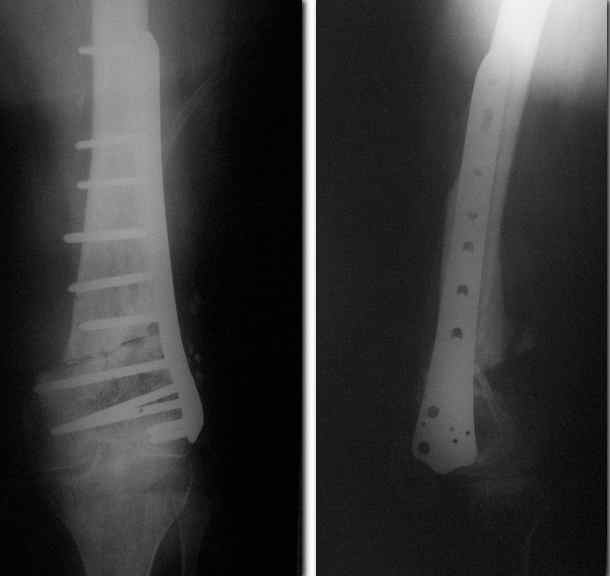

Пример подобного ложного сустава в приложении.

На сегодня есть имплантаты с куда более продвинутой дистальной фиксацией.

Да практически у всех производителей есть сегодня бедренные стержни с возмоностью ввести винты максимально дистально, и более 2. Это и Synthes, и Stryker, и DePuy, и ChM, и даже предприятие "ЦИТО". Единственное - диаметр винтов. Желательно больше 5 мм.

В конце концов, можно в таком единичном случае вспомнить о замечательном научно-практическом направлении - гаражной ортопедии. Взять стержень диаметром мм 13 прежнего дизайна, т.е. с двумя отверстиями, да и просверлить еще несколько, можно не только во фронтальной плоскости.

Спасибо. Прооперировали во вторник.

Выглядит красиво. А движения в колене какие были на столе?